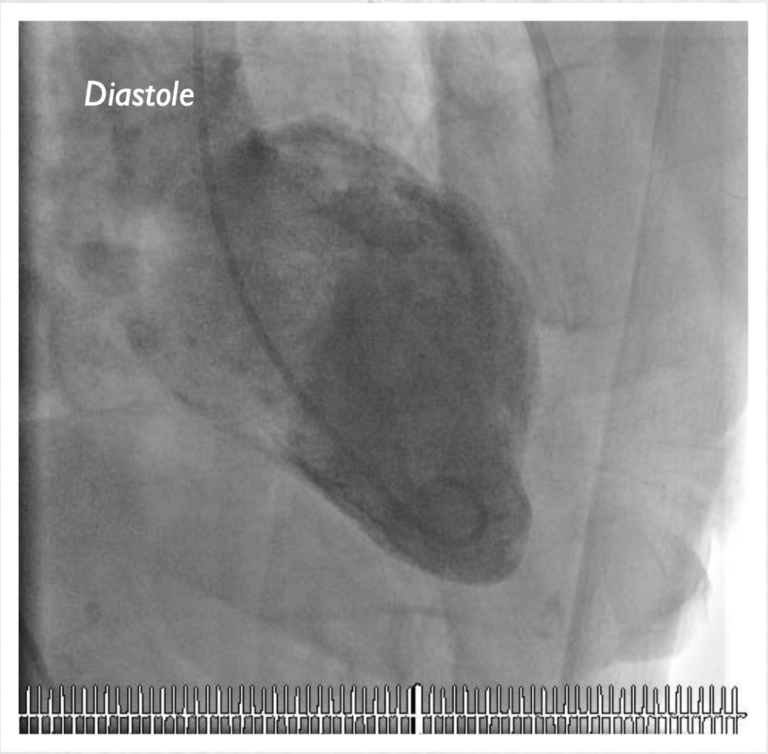

要区分心碎综合征和心脏病发作(心肌梗塞),就需要在急性发作期进行冠状动脉造影和左心室造影(左心室衬度成像)。由于左心室的成像与历史上日本人用来捕捉章鱼、一类带有细颈和球根状的砂锅十分相似,因此用“章鱼壶”一词来描述。心碎综合征与典型心脏病发作之间的最大区别是,前者在冠状动脉造影时没有发现冠状动脉阻塞。